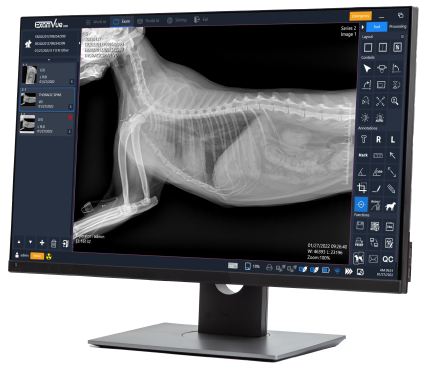

Powered by ExamVue™ Acquisition Software

DynaVue™ Duo is powered by

Specialized Tools for Veterinarians

🔹Axial Angle

🔹Clock Face

🔹Clock Face (Lat View)

🔹Clock Face (VD View)

🔹Cross Angle

🔹Liver Size

🔹Middle Angle

🔹Norberg Angle

🔹Percent Coverage

🔹Spine Label

🔹TPA

🔹Vertical Discrepancy

🔹VHS

🔹VLAS

🔹Vertebral Heart Score

🔹Norberg Hip Analysis

🔹TPLO Analysis

🔹TTA Analysis